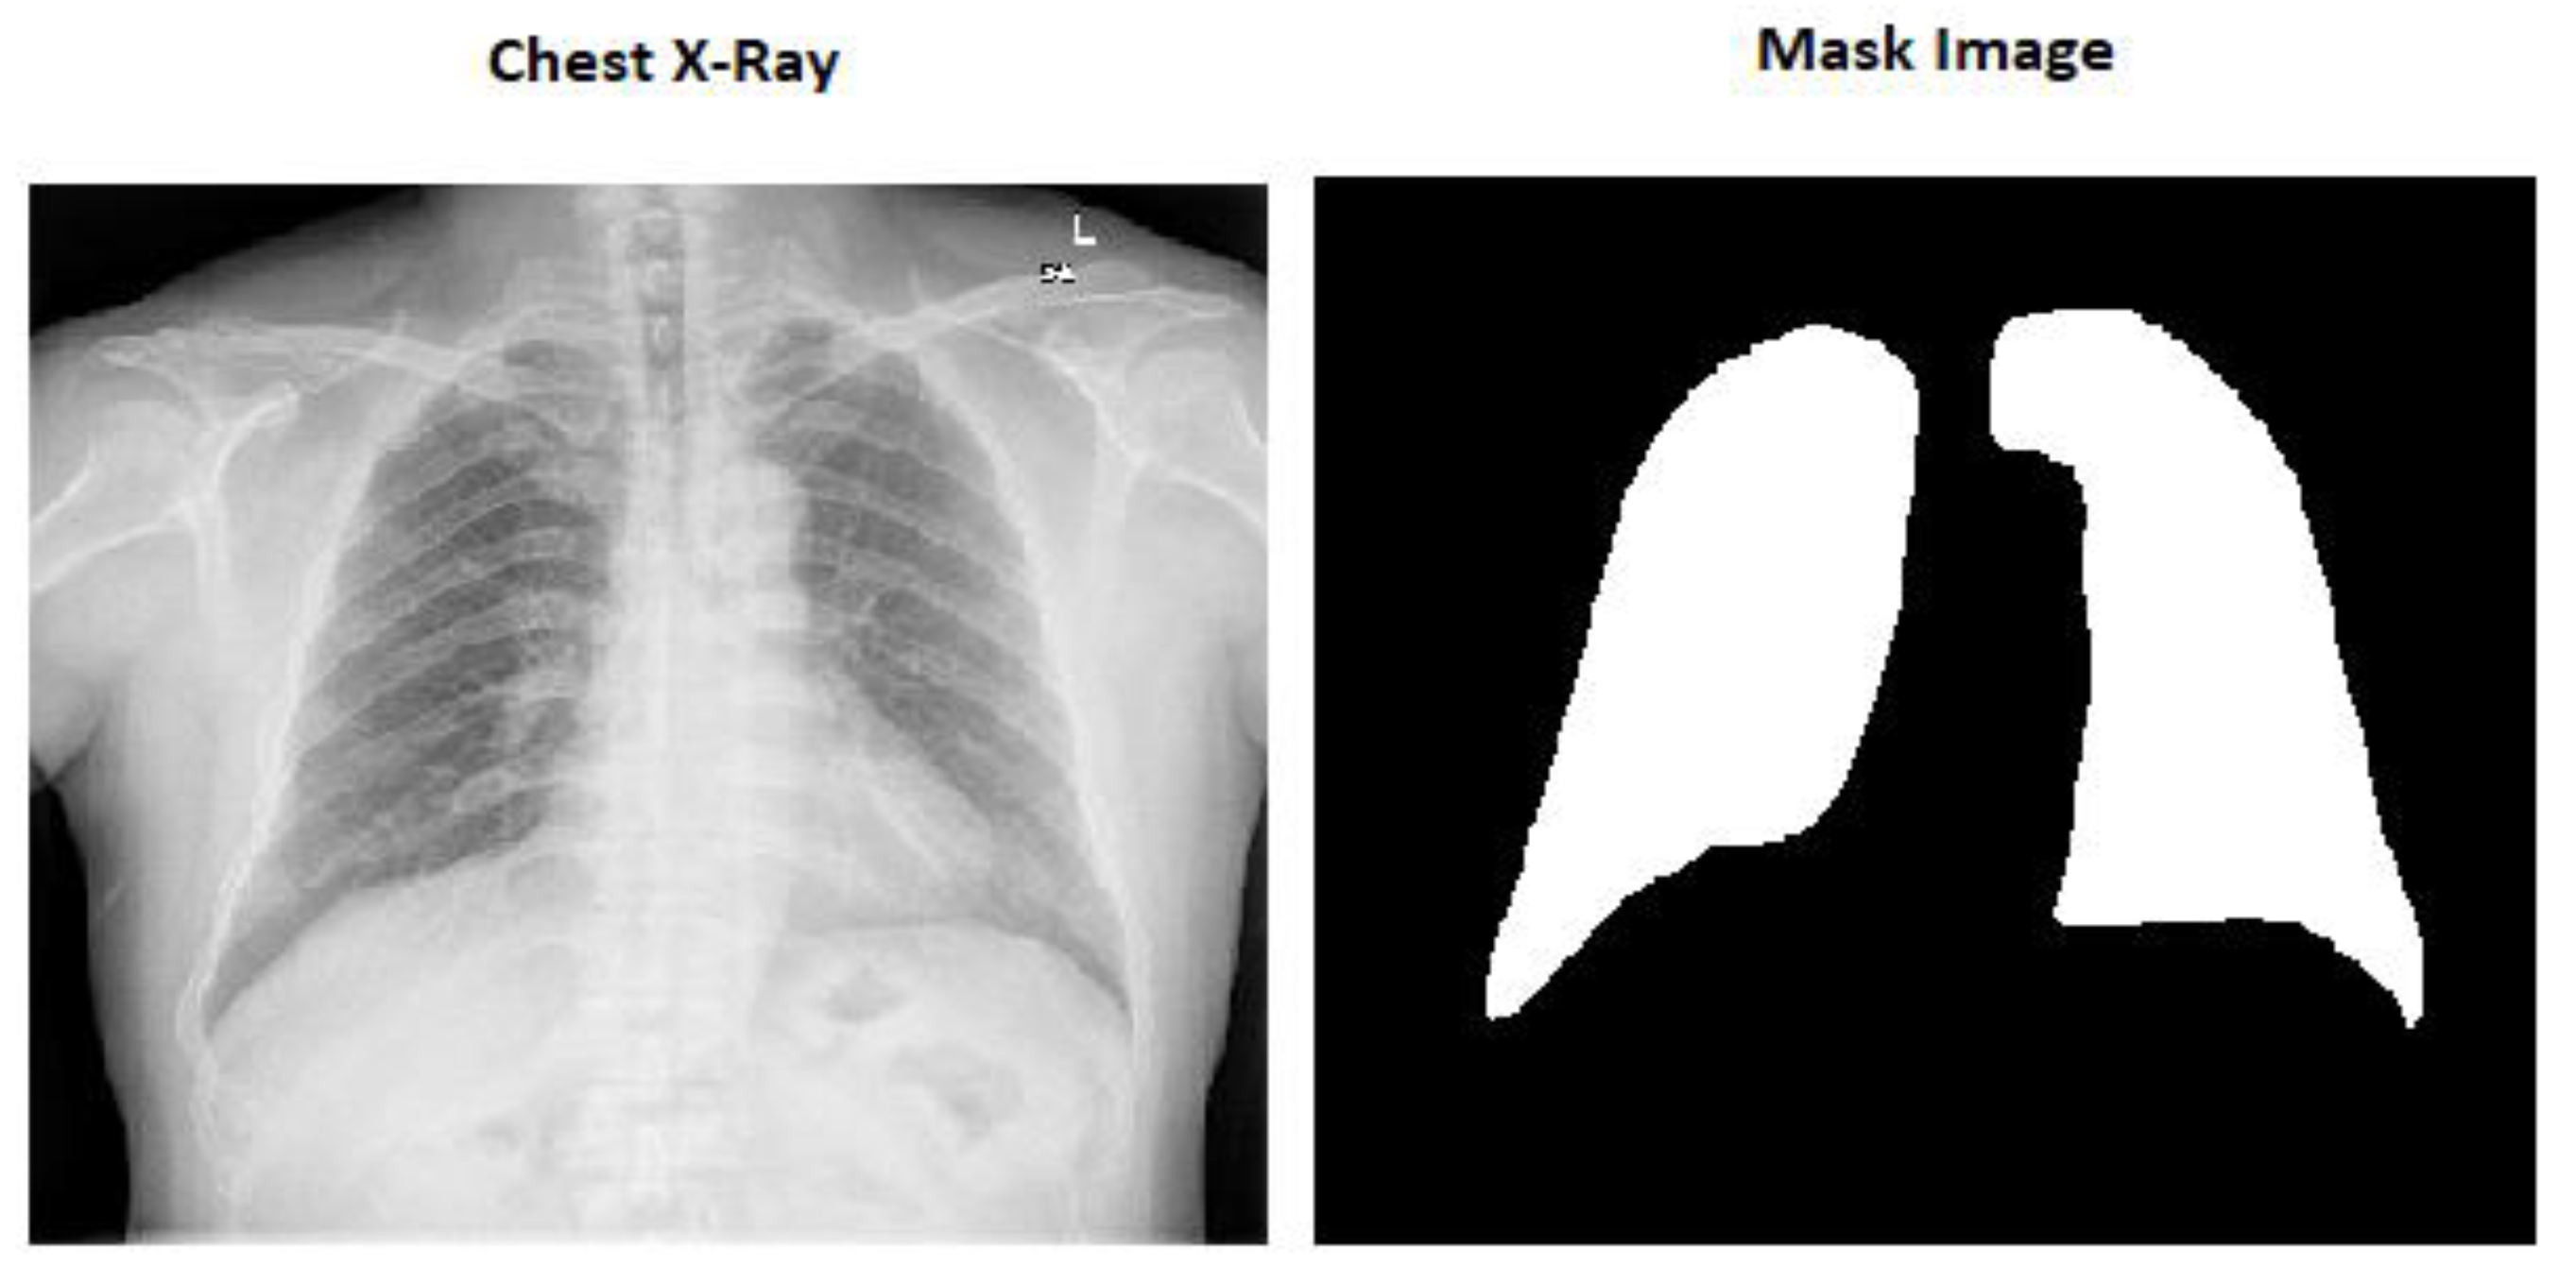

The mask pictures are included in all the chest X-ray images in the dataset. There are 800 chest X-ray pictures and 704 mask images in all.

Here in Figure 1 we can see the image size is (256 × 256 × 3) which is the actual size of the image and Figure 2 is the modified image which is (256 × 256 × 1).

Figure 1.

Chest X-ray image (256 × 256 × 3) size.